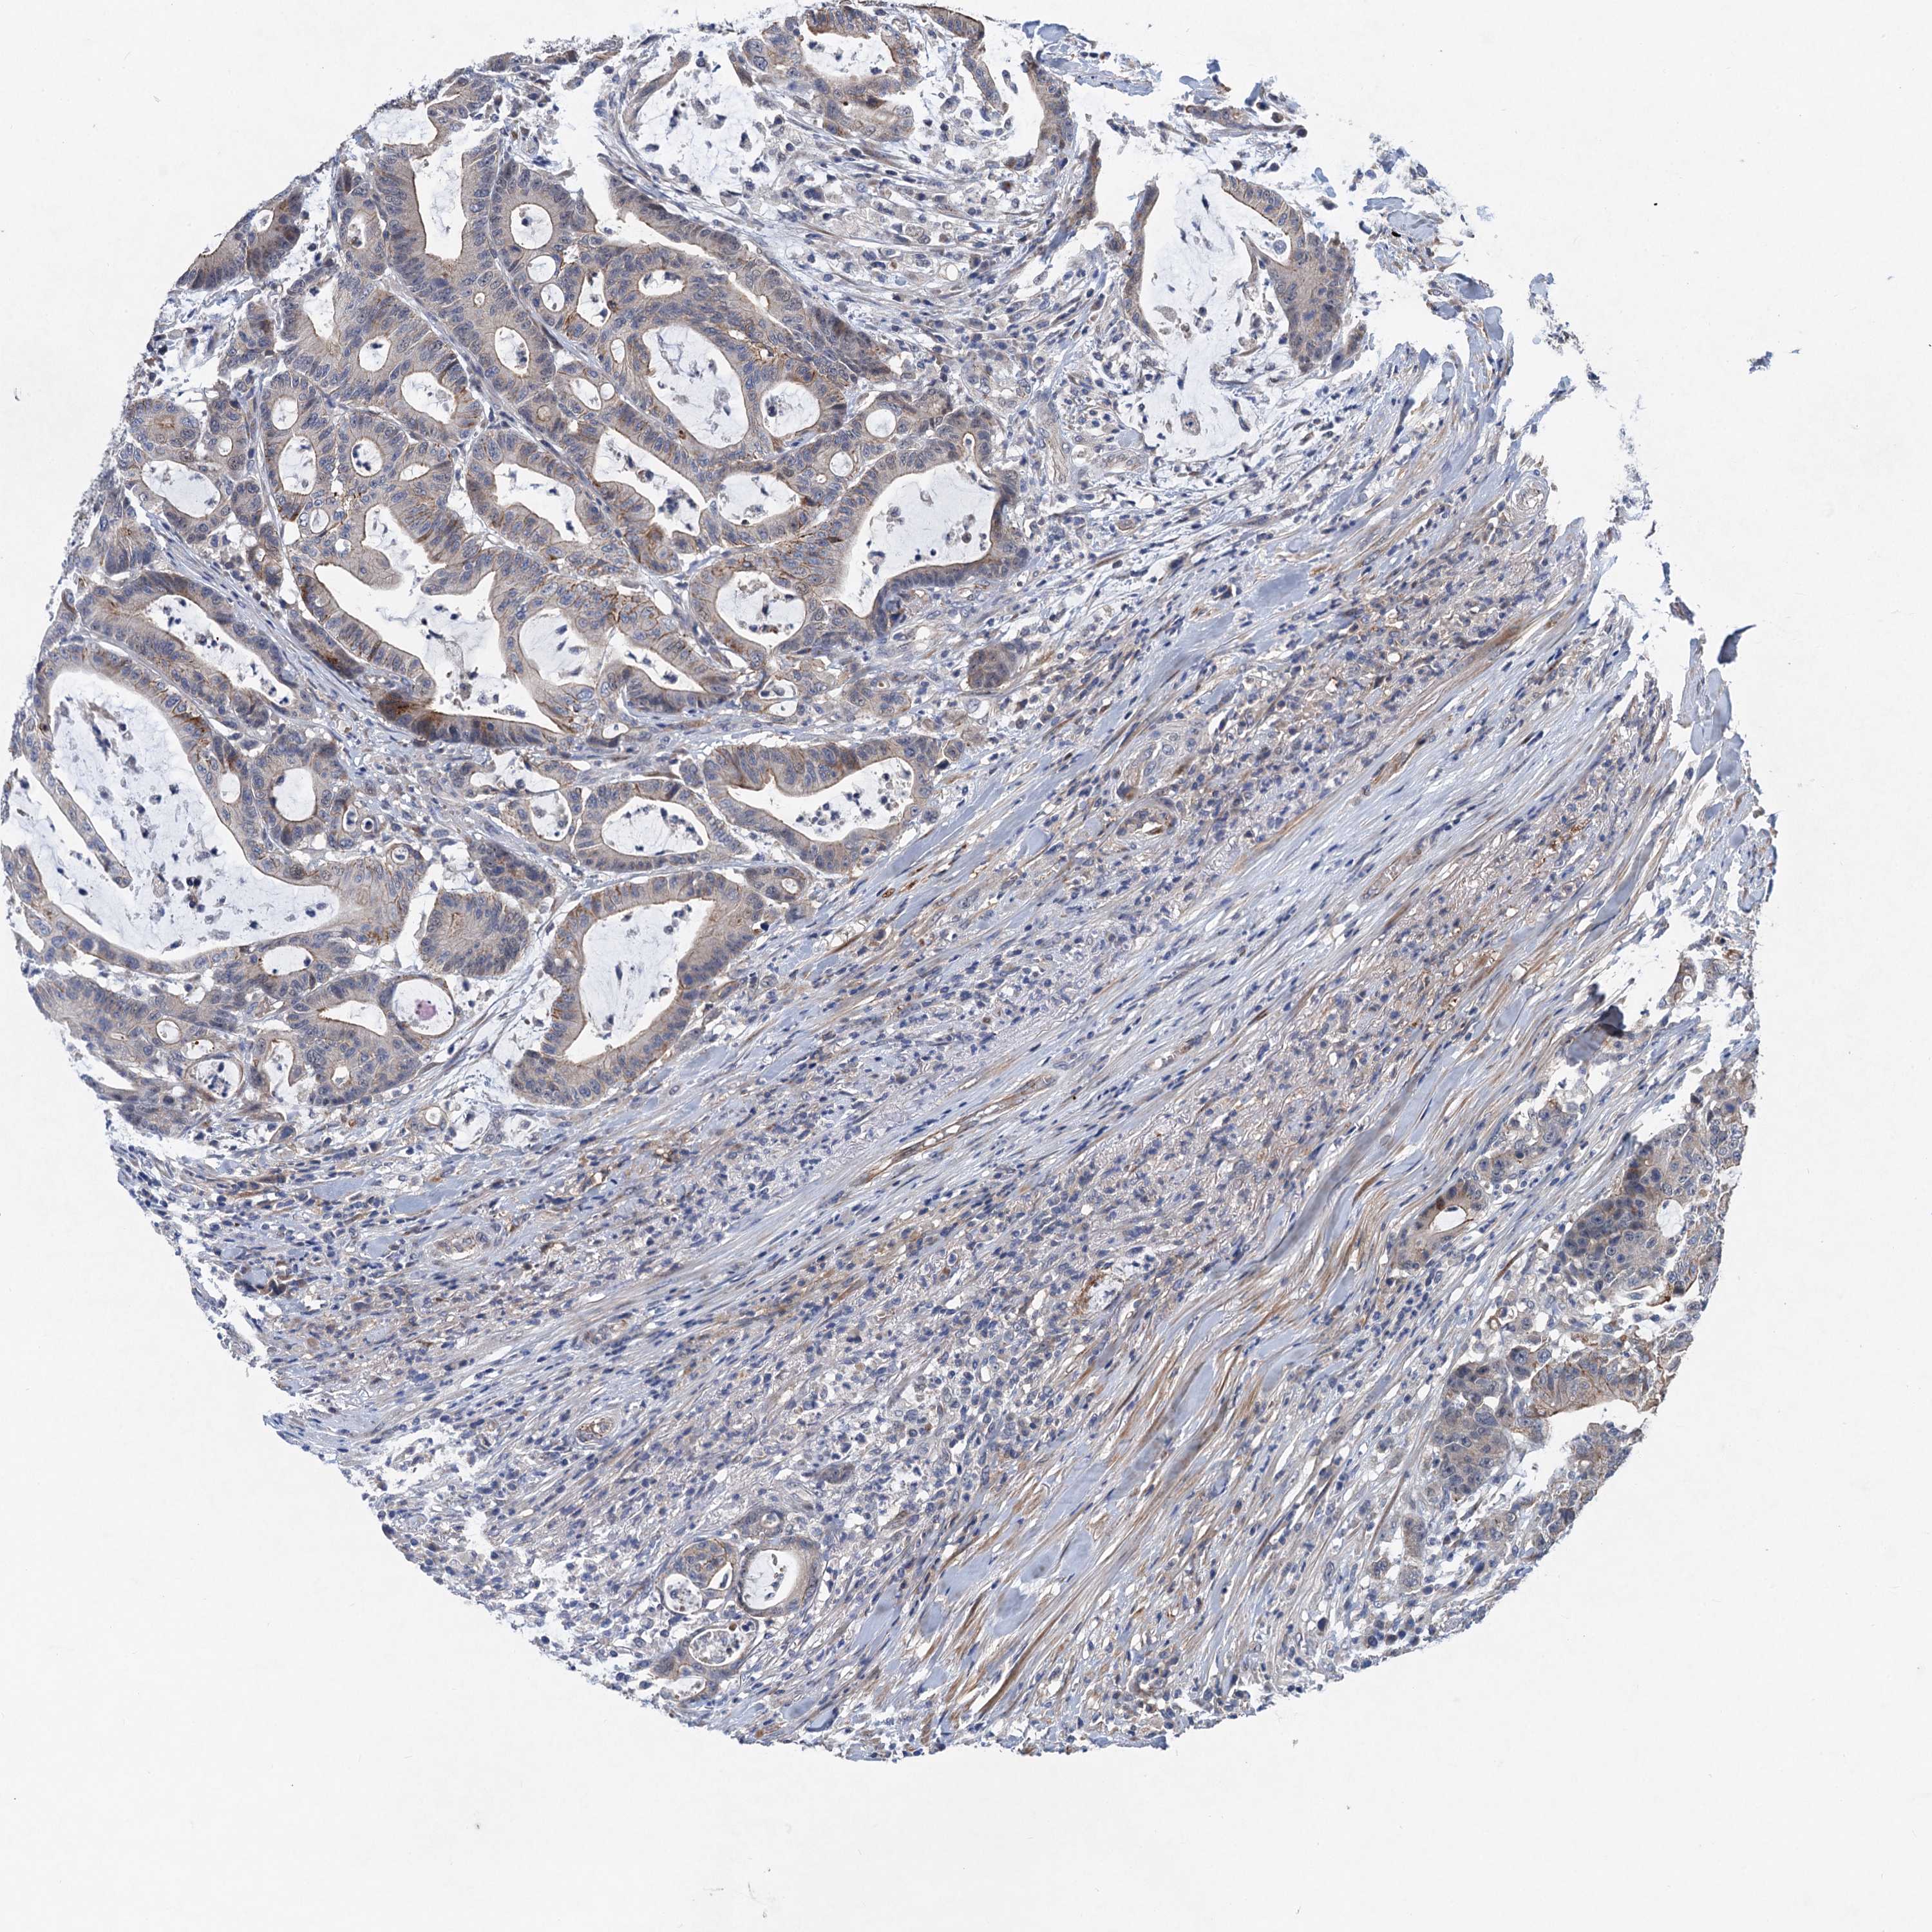

CANCER COLORECTAL CANCER Show tissue menu

Colorectal cancer

Human cancer

Colon adenocarcinoma